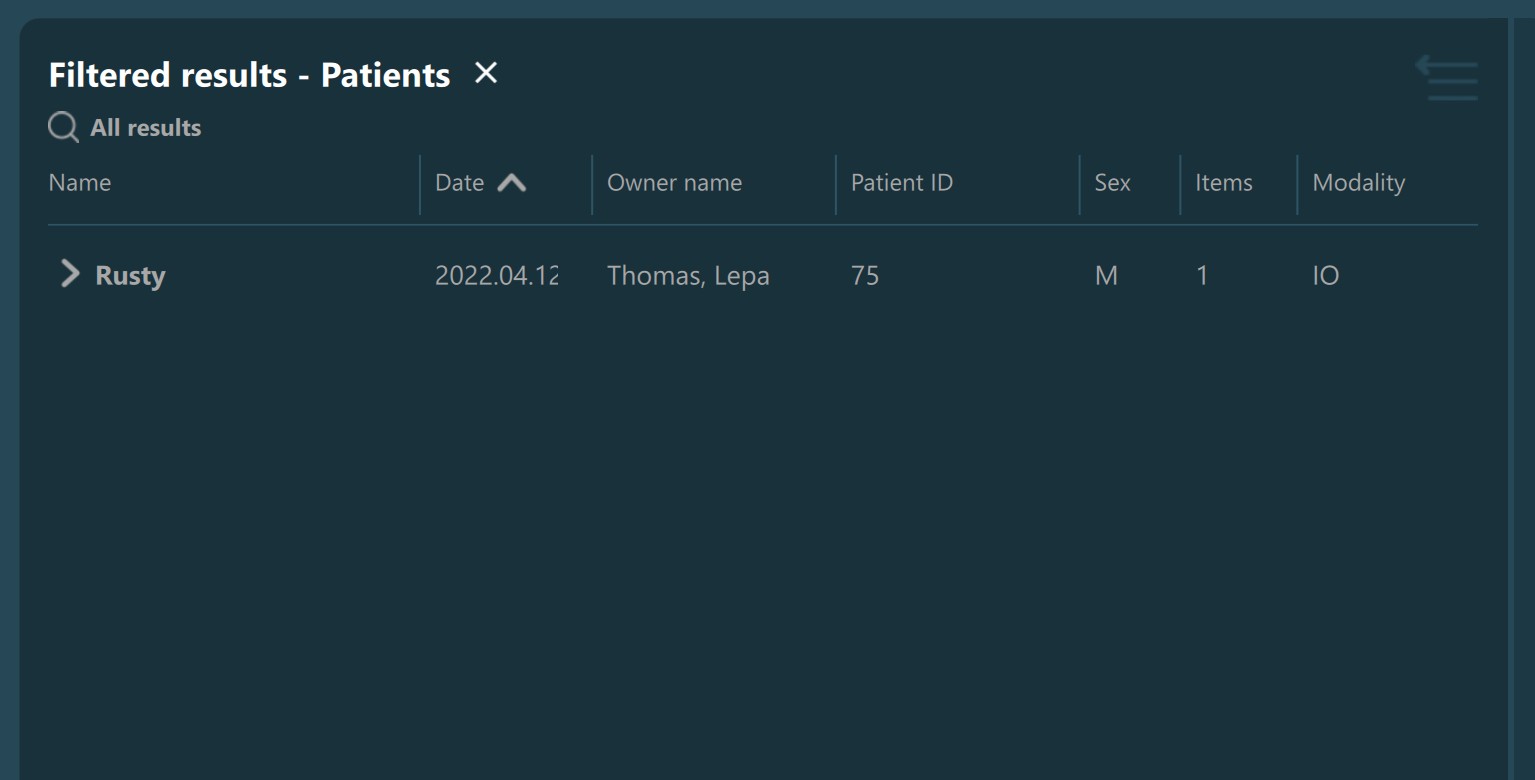

Filtered Study List information with exact and similar matches found:

Filtered Study List information with only similar matches found:

Filtered Study List information with only exact matches found:

Filtered Study List information with no exact and similar matches found will display the No matches found… entry in the Study List.